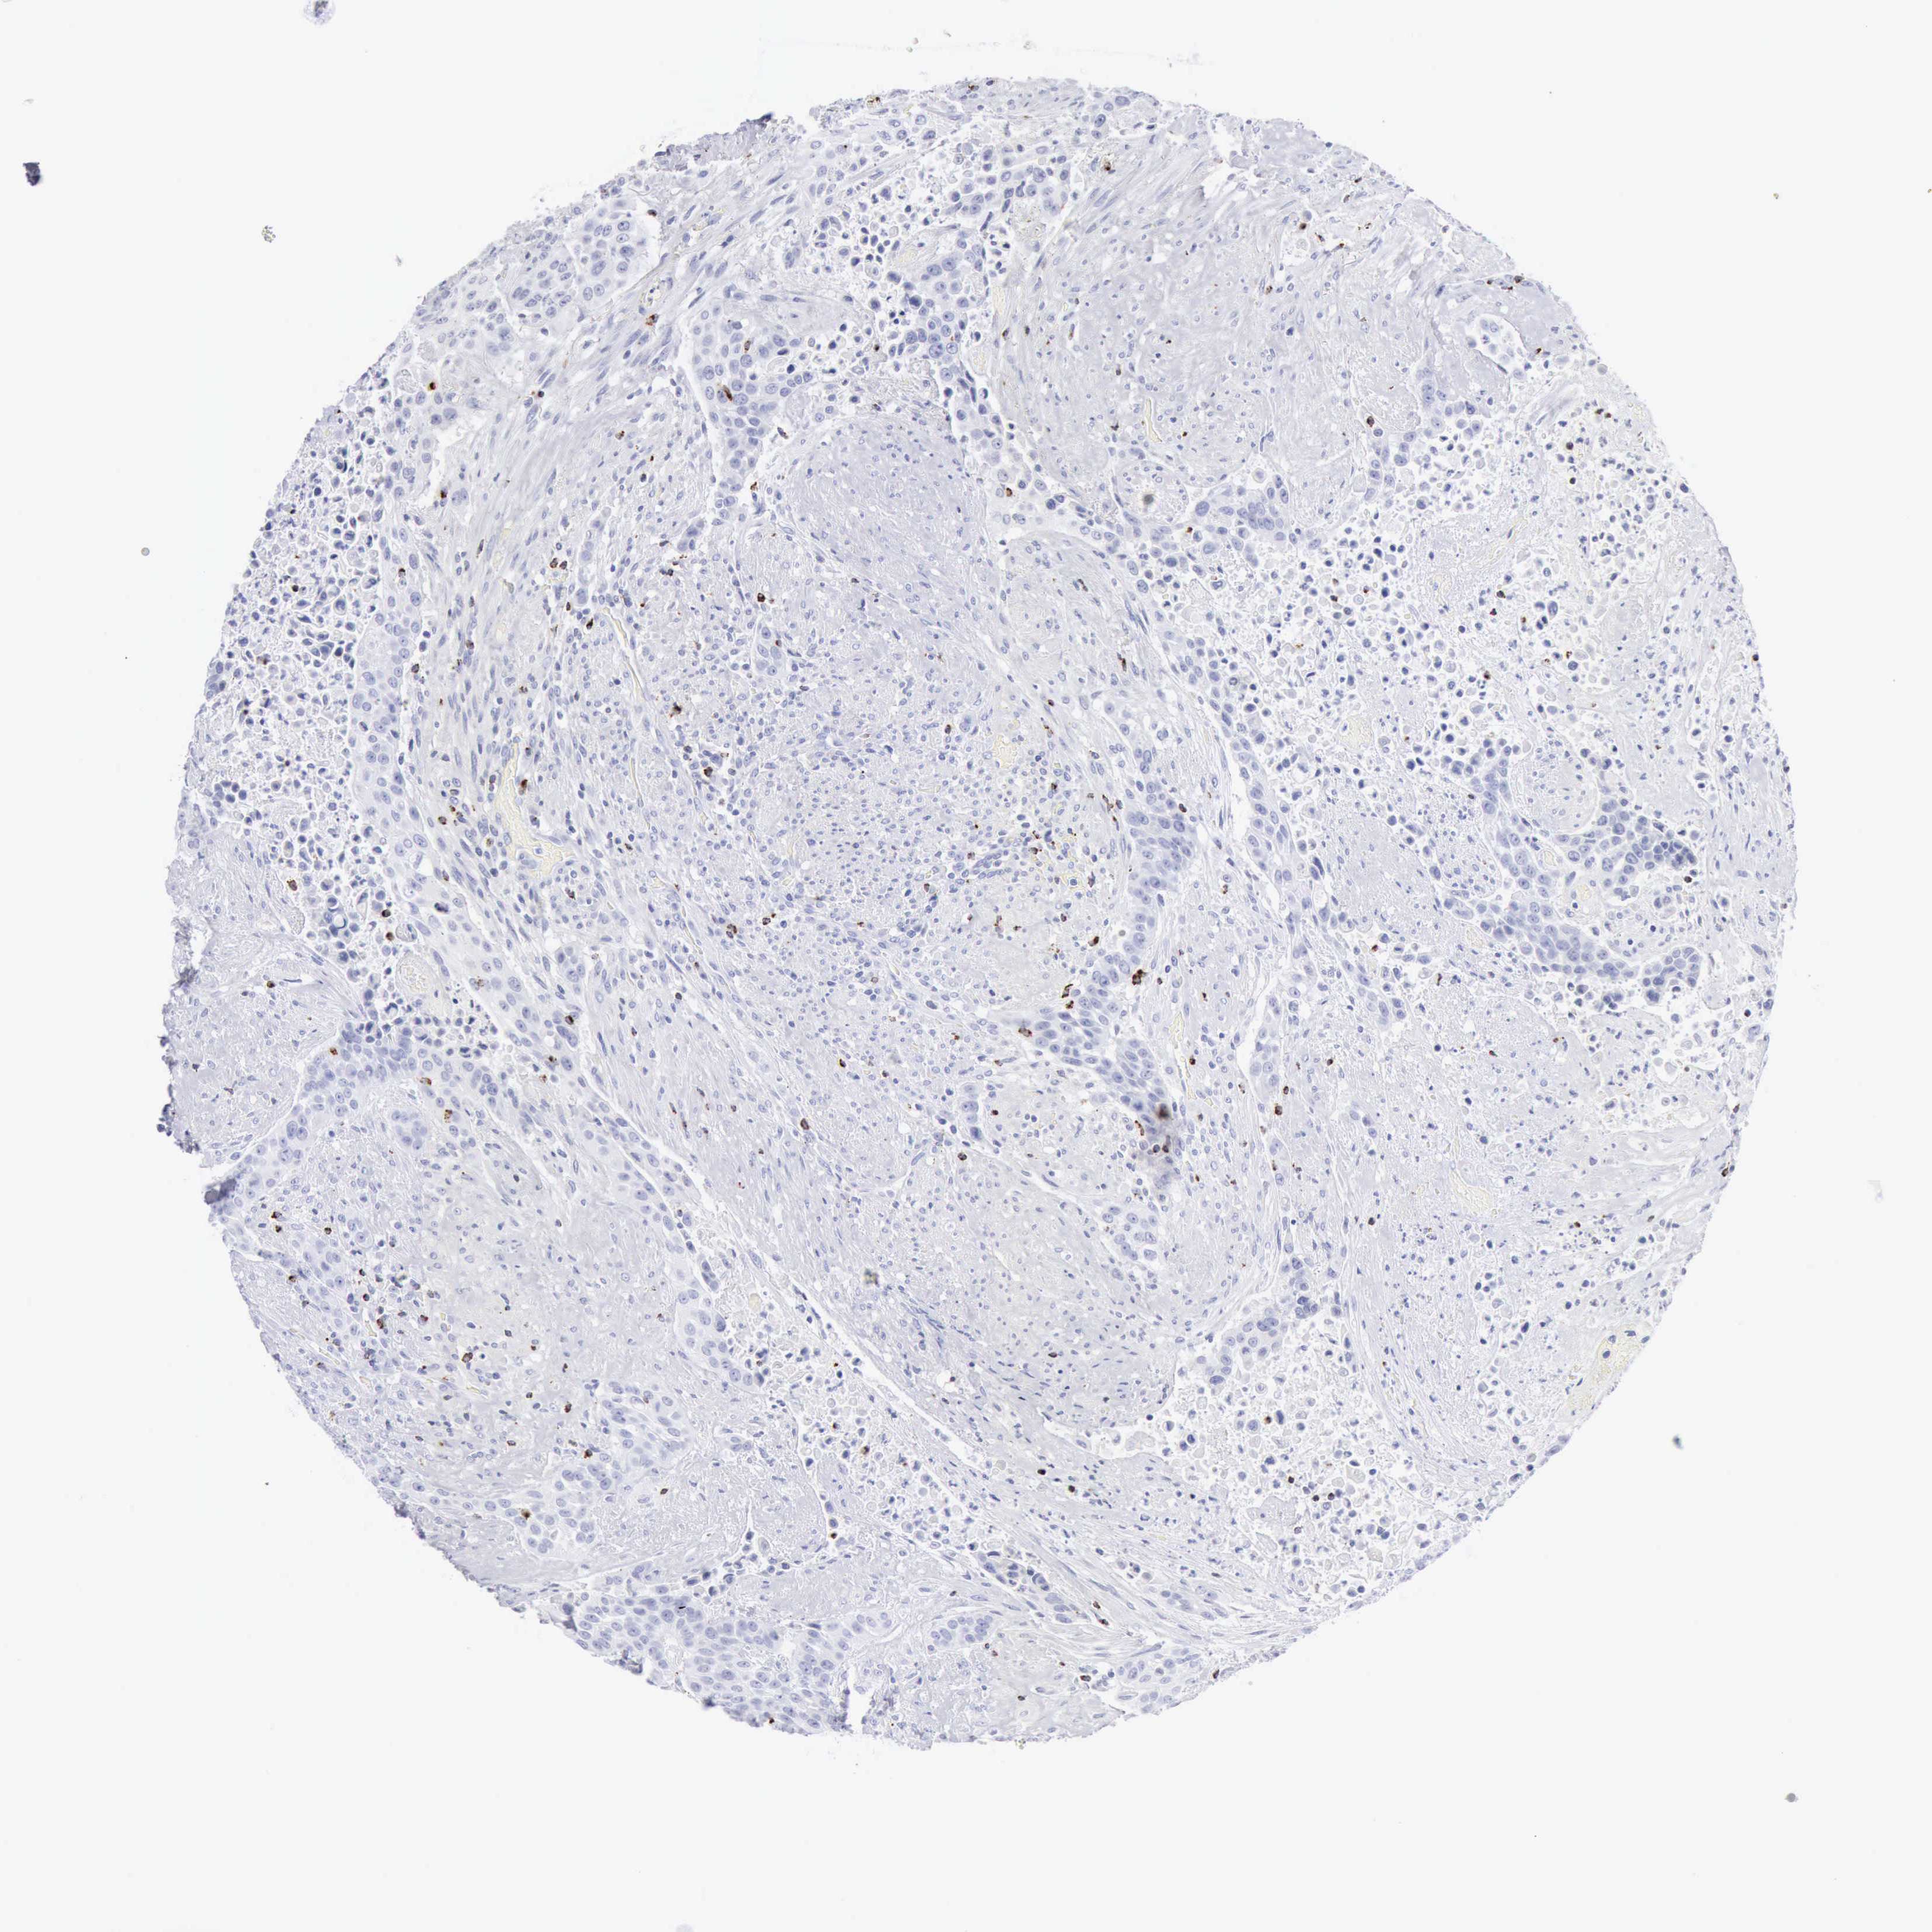

UROTHELIAL CANCER - Protein expressioni

A mouse-over function shows sample information and annotation data. Click on an image to view it in a full screen mode. Samples can be filtered based on level of antibody staining by selecting one or several of the following categories: high, medium, low and not detected. The assay and annotation is described here.

Note that samples used for immunohistochemistry by the Human Protein Atlas do not correspond to samples in the TCGA dataset.

Antibody stainingi

Antibody staining in the annotated cell types in the current human tissue is reported as not detected, low, medium, or high, based on conventional immunohistochemistry profiling in selected tissues. This score is based on the combination of the staining intensity and fraction of stained cells.

Each image is clickable and will lead to virtual microscopy that enables deeper exploration of all samples and also displays staining intensity scores, fraction scores and subcellular localization as well as patient and tissue information for each sample.

Antibody HPA003418

Antibody CAB000376

Urothelial carcinoma, High grade

Urothelial carcinoma, Low grade